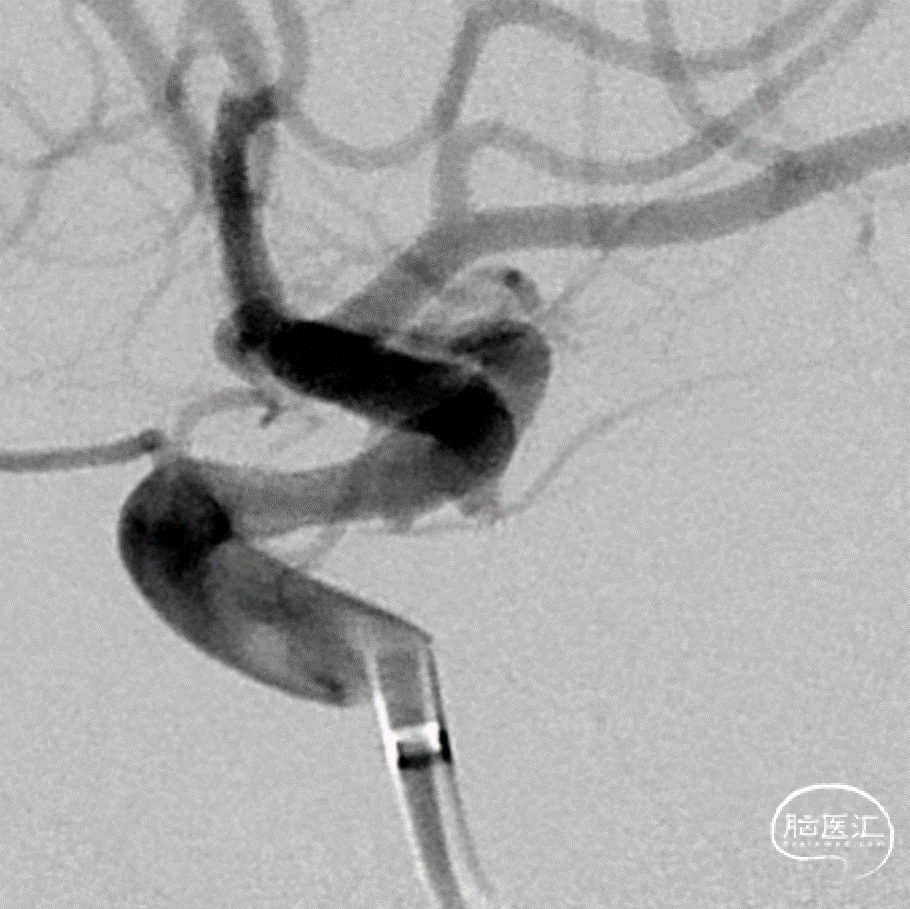

工作角度造影

Roadmap

微导管超选

Galaxy G3 MINI 1mm*1cm的mini(强生)

术后情况/术后即刻:动脉瘤不显影

术后3D重建:动脉瘤不显影,载瘤动脉通畅